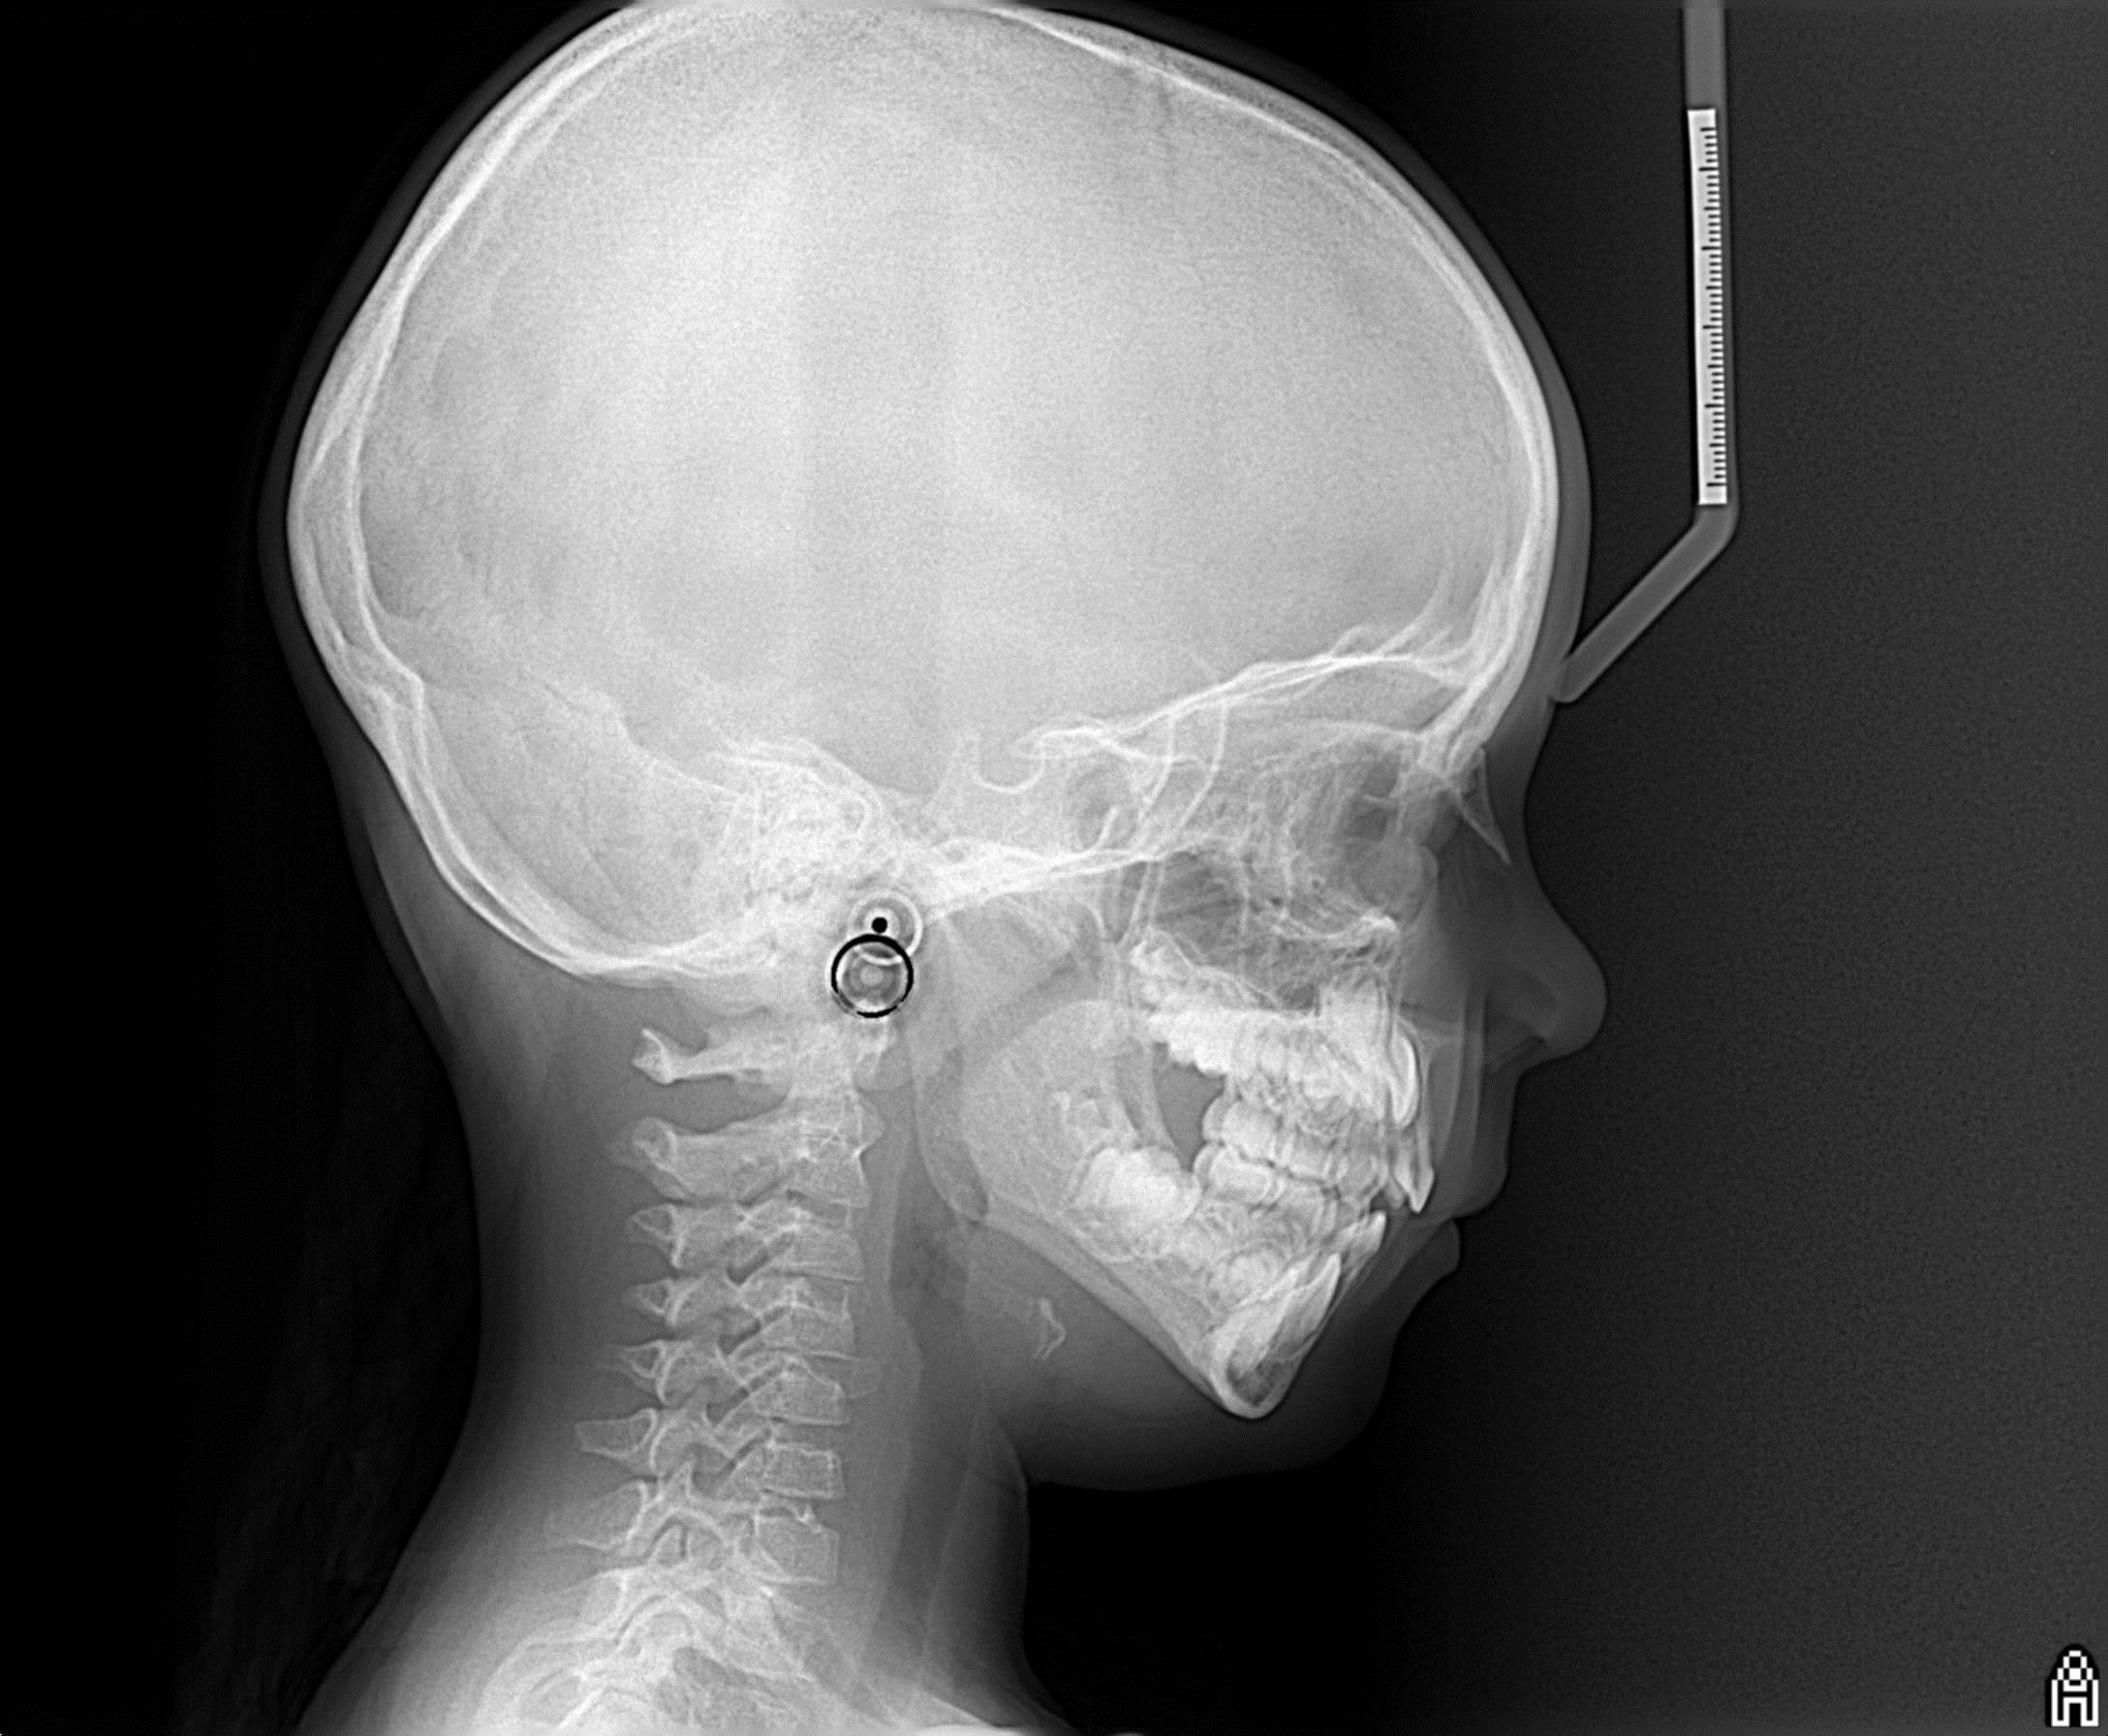

bilan des radiographies début et en cours de traitement